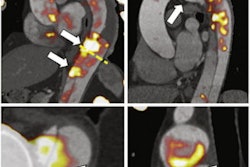

The Aura 10 is the first PET/CT specimen scanner for use in operating rooms, according to the company. The scanner is mobile and offers surgeons and imaging specialists the ability to acquire high-quality images in the operating room within 10 minutes after excision without having to transport samples to radiology or pathology departments during surgery.